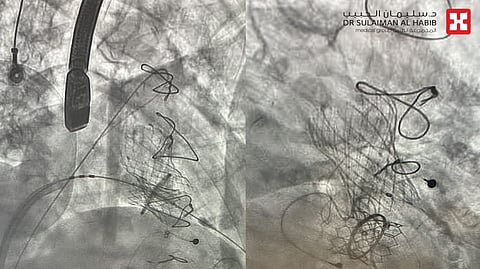

وبالفعل، أُجريت للمريضة عملية دقيقة استمرت 90 دقيقة، تم خلالها زراعة صمام خارجي بديل للميترالي بهدف التخلص من التسريب والتضيق، وتكللت العملية بالنجاح التام، حيث نُقلت المراجعة بعد العملية إلى العناية المركزة بمؤشرات حيوية مستقرة، ووُضعت تحت المراقبة لمدة 48 ساعة.

وأظهرت صور الأشعة والأشعة الصوتية عبر البلعوم استعادة الصمام لوظائفه بالكامل دون تسريب أو تضيق، كما لم تتأثر الصمامات الأخرى، خصوصًا الصمام الأورطي المزروع سابقًا. وبعد أيام قليلة، غادرت المراجعة المستشفى بحالة صحية مستقرة بعد أن تخلصت من الأعراض التي كانت تعانيها.